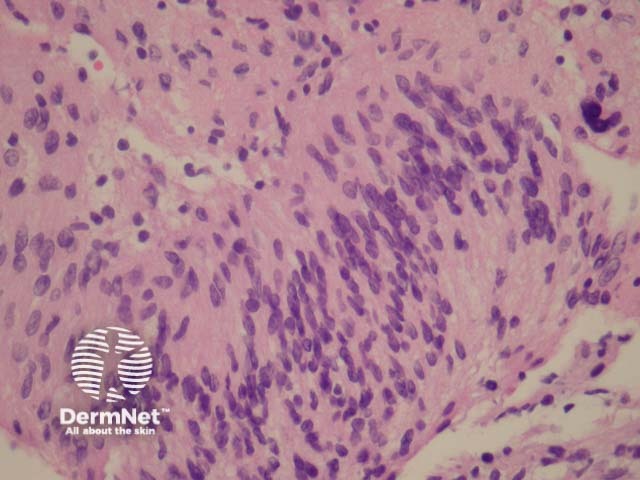

In schwannoma, sections show an encapsulated well-circumscribed lesion beneath the uninterrupted epidermis. The tumour is composed of different areas composed of different cellular densities. More cellular areas (Antoni A, figure 1) are composed of a haphazard arrangement of bland cells with spindled and oval nuclei. Loose, less cellular areas (Antoni B, figure 2) are composed of a loose oedematous and mucinous stroma with fibrillar collagen. The vessels are prominent and often surrounded by a dense sclerosis.

Figure 2